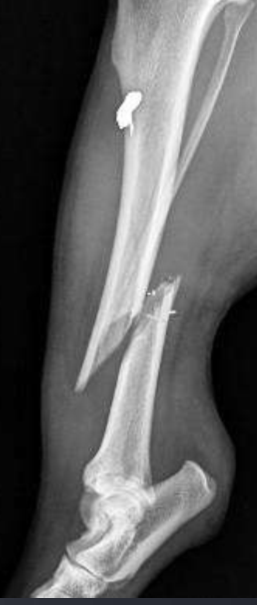

metal opacity from a ballistic

What are causes of metal opacity in soft tissue?

Ballistics

Implants

Microchip